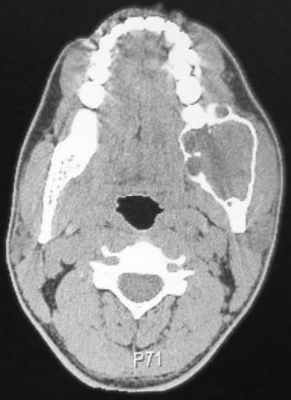

Клинический случай №4

Пациент муж., 32 года (Рис. 5).

Рис. 5. КТ свидетельствует об объемном образовании нижней челюсти, требующем верификации.

Поражена правая ветвь нижней челюсти. Определяется объемное кистозное образование, овальной формы с четкими полицикличными контурами, замещающее весь венечный отросток и распространяющееся на суставной отросток. Объем кости увеличен за счет вздутия. Кортикальный слой значительно истончен, местами не прослеживается. Канал нижнеальвеолярного нерва вплотную прилежит к образованию, верхняя его стенка в проксимальном отделе не прослеживается. В подьязычной области справа виден лимфоузел, размерами 1,7 на 0,9 см.